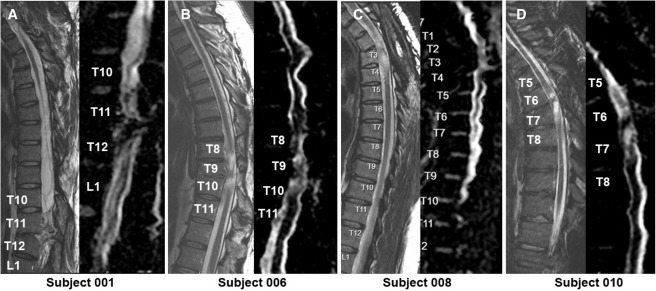

4.影像學(xué)評(píng)估:術(shù)后MRI顯示所有患者存在不同程度的局灶性脊髓軟化,但未見新的并發(fā)影像學(xué)征象(如水腫、增強(qiáng)或積液);DTI提示脊髓束外觀穩(wěn)定,未見廣泛重塑或纖維束改善。

MRI頸胸T2矢狀圖和AvDC矢狀圖